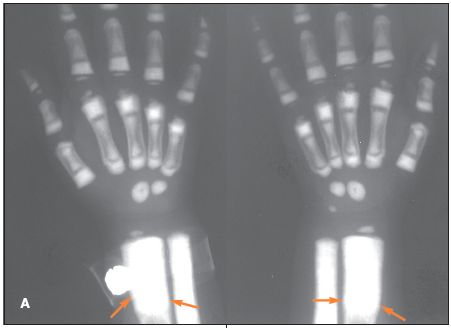

The radiographs demonstrate prominent soft tissue and bone overgrowth in the finger, consistent with the clinical and radiographic diagnosis of megadactyly. The soft tissue overgrowth is most marked at the distal end of the digit and the volar aspect. The intermetacarpal space is also enlarged. The finger has a slight lateral curve at the apex but no underlying bone deformity. Several lucent areas represent fat. Macrodystrophia lipomatosa was the subsequent diagnosis.

The child has osteopetrosis. The radiographs show diffuse osteosclerosis and dramatically increased bone density throughout the axial and appendicular skeleton. There is diffuse bone sclerosis in the hands with widening of the distal radial metaphyses (A, arrows) and a "bone-within-a-bone appearance"--typical of osteopetrosis--in virtually all the metacarpals and phalanges. Bone sclerosis is also apparent in the feet; the bone-within-a-bone appearance is most prominent in the metatarsals (B, arrows). A chest radiograph demonstrates diffuse bone sclerosis and numerous old fractures of the anterolateral ribs bilaterally (C, arrows).